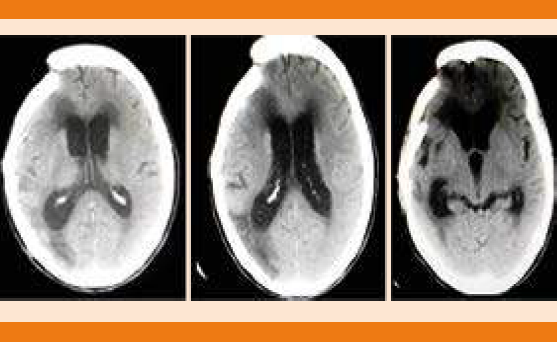

Paciente femenina de 68 años de edad, con antecedente de hipertensión arterial sistémica y cirugía de clipaje por hemorragia subaracnoidea 14 años antes. Ingresó por pérdida del estado de alerta, crisis convulsivas tónico-clónicas generalizadas y deterioro neurológico con puntaje de acuerdo con la escala de coma de Glasgow de seis puntos a expensas de: respuesta ocular: un punto, respuesta verbal: dos puntos y respuesta motora: tres puntos, de 12 horas de evolución. A su ingreso en el servicio de Urgencias se decidió dar manejo avanzado de la vía aérea, vasopresor e inotrópicos, así como cuidados de paciente neurocrítico. La tomografía de cráneo simple evidenció imagen hipodensa en la región frontotemporal derecha sugerente de infarto que correspondía al territorio de la arteria cerebral media derecha y cambios posquirúrgicos asociados (Figura 1). El electrocardiograma de 12 derivaciones mostró desnivel positivo en la cara anterior extensa, lesión subepicárdica en la cara anterolateral extensa, desnivel negativo en la cara inferior, lesión subendocárdica inferior, sin datos de isquemia o necrosis (Figura 2). Biomarcadores de lesión cardiaca: troponina 2.1, CK 232, CK-MB 33. Por los cambios encontrados en el electrocardiograma y el incremento de biomarcadores cardiacos se realizó coronariografía en la fase aguda para excluir oclusión coronaria que reportó ausencia de lesiones estenóticas o placas de ateromas en la circulación coronaria derecha e izquierda. En los ventriculogramas se observó dilatación apical fija e hipocinesia con movilidad conservada en las bases. Insuficiencia mitral leve. Presión telediastólica del ventrículo izquierdo de 18 mmHg y fracción de eyección del ventrículo izquierdo de 40% (Figura 3). El desenlace de la paciente lamentablemente fue funesto.

Figura 1 Tomografía de cráneo simple que muestra cambios posquirúrgicos por área de craniectomía frontoparietal derecha, dos imágenes hipodensas en sitio de la arteria cerebral posterior en la región parietooccipital derecha, ventriculomegalia, imagen lineal hiperdensa, encefalomalacia.